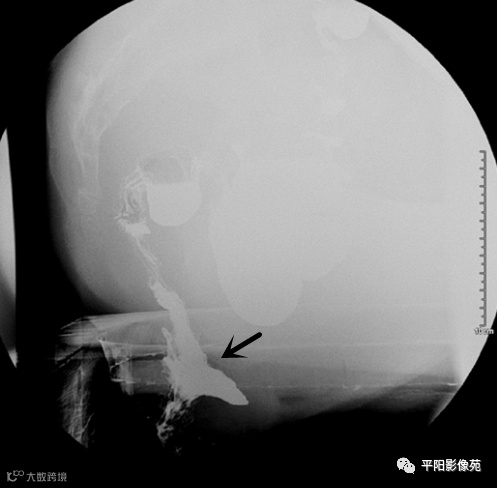

直肠内套叠(internal rectal intussusception,IRI)又称直肠隐性脱垂。有两种情况,①直肠内黏膜套叠:增粗而松弛的直肠黏膜脱垂,在直肠内形成约3mm的环形套叠;②直肠内全层黏膜套叠:脱垂的直肠黏膜形成的环形套叠厚度>5mm。按套叠的部位分为:近段套叠、远段套叠、直肠套入肛管等3种。套叠可合并其他异常,或多发或多重套叠。(图3)

图3 直肠内黏膜紊乱、堆积并套入肛管内